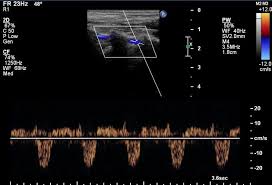

The left vertebral artery spectral wave doppler is seen below the baseline as compared to both left CCA and right vertebral artery. Subclavian steal syndrome occurs secondary to a proximal stenosing lesion or occlusion in the subclavian artery. Features are characteristic of complete left subclavian steal syndrome Features are characteristic of complete left subclavian steal syndrome.